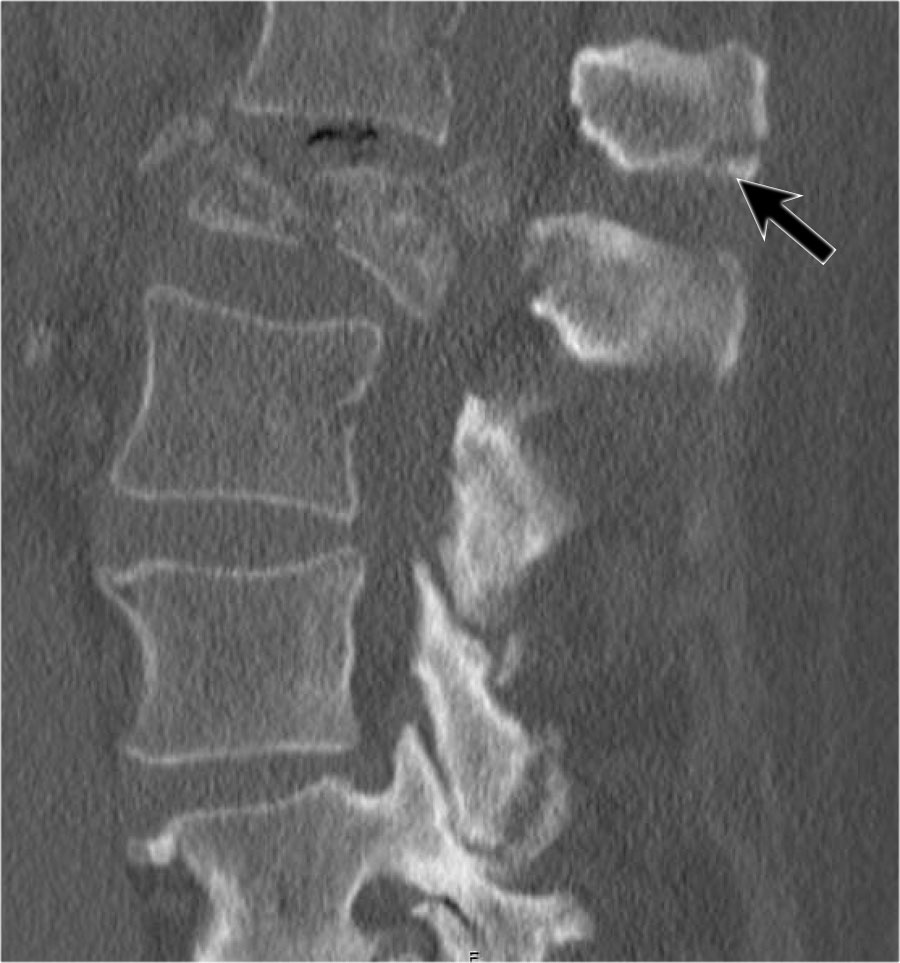

Giãn rộng khoảng cách liên cuống (interpedicular distance)

Giãn rộng khoảng cách liên cuống, thường là hệ quả của đường gãy theo mặt phẳng đứng dọc, gặp trong 80% các trường hợp gãy vỡ.

Hình chiếu bên cho thấy các đặc điểm điển hình của gãy vỡ.

Trên hình chiếu thẳng (AP), lưu ý sự giãn rộng kín đáo của khoảng cách liên cuống so với các tầng trên và dưới.

CT axial và MRI trên cùng một bệnh nhân cho thấy mảnh xương di lệch đang chèn ép vào bao màng cứng (thecal sac).

Trên CT và MRI mặt phẳng đứng dọc, không có dấu hiệu tổn thương dây chằng phía sau.

Dây chằng dọc trước bị đứt.

Khớp mặt bên phải trông hơi giãn rộng trên CT và có dịch trong khớp trên MRI.

Nếu có nhiều dịch trong khớp, chúng ta nên xếp loại là không xác định.

Trong trường hợp này, chúng ta chưa chắc chắn.